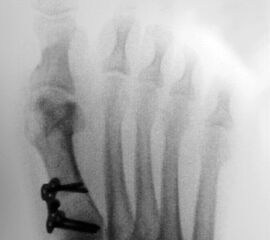

Abbildung 1

• Röntgenaufnahme des Fußes unter Belastung in d.p., schräg und seitlichem Strahlengang.

• Beurteilung des Intermetatarsalwinkels (IMA) und des distalen und proximalen Gelenkwinkels (DMAA, PMAA) (Abb. 1).

• Planung der Korrekturosteotomie: 1 mm Plattensteg korrigiert etwa 2° Intermetatarsalwinkel.

• Planung der Osteotomie mit ausreichendem Abstand vom Tarsometatarsale I Gelenk (ca. 1 cm). Vor allem bei sehr schräg angelegten Tarsometatareale I Gelenken besteht das Risiko mit den proximalen Schrauben in das Gelenk vorzudringen.